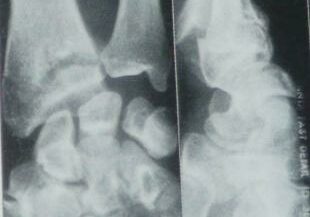

Ostéosynthèses de fractures du poignet

L’ostéosynthèse de fractures du poignet est une intervention chirurgicale réalisée pour réparer une fracture de l’os du poignet (fracture du radius, du cubitus ou d’autres os du carpe) en utilisant des implants tels que des vis, des plaques, des broches ou des clous pour maintenir les fragments osseux en place pendant la guérison. Cette procédure vise à restaurer l’alignement normal de l’os fracturé et à favoriser une guérison adéquate.